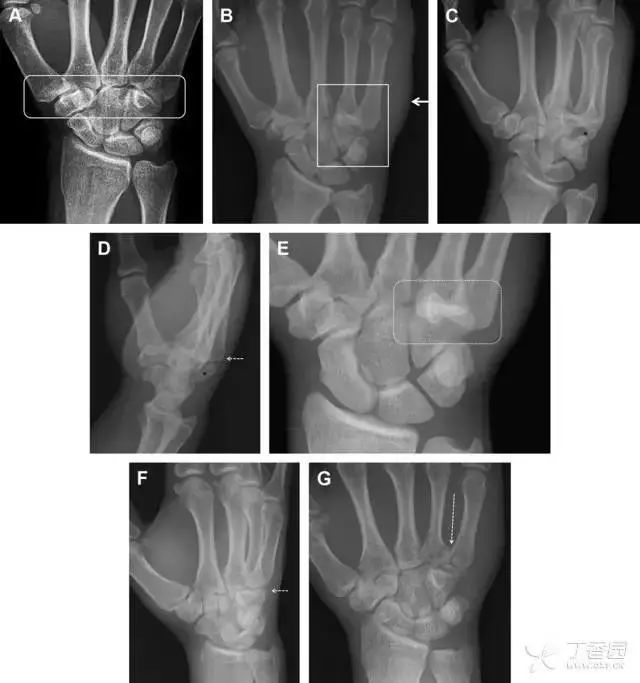

桡骨远端骨折

常规进行前后位、侧位、斜位 X 线检查,对于大多数桡骨远端骨折来说不容易漏诊;但是对于无移位的骨折,特别是桡骨茎突骨折,容易漏诊。桡骨茎突骨折是一斜行的骨折,常累及关节面,常发生于轴向应力或直接打击。

图 1 57 岁女性,摔倒后手掌撑地,桡骨茎突压痛。(A~C)前后位、斜位、侧位片示软组织肿胀(*)和发丝样骨折(白色箭头);(D~F)2 周后,前后位、斜位、侧位片示骨折线显明,由于新骨痂沉积而呈现透亮线与硬化线并存;(G~I)另一患者,桡骨茎突骨折在前后位及侧位片上显示不明显,而在斜位片显示更清楚。

舟状骨骨折

舟状骨骨折 60%~70% 发生于腰部,15% 发生于近极, 10% 发生于远极, 8% 发生于远端关节面。除了常规的前后位、侧位、斜位片外,还需要拍专门的舟状骨位片(腕关节尺偏,以舟状骨为中心的腕关节前后位片),特别是鼻烟壶有压痛时。

图 2 舟状骨骨折 (A、B)第 1 例患者,舟状骨远极关节内骨折(白色箭头),斜位片显示较清楚(B);(C、D)第 2 例患者,舟状骨腰部骨折(虚线箭头),斜位片显示较清楚(D);(E~H)第 3 例患者,舟状骨近极骨折,常规 X 线片均未看到骨折,而在舟状骨位片上才能见到骨折(虚线圆)。